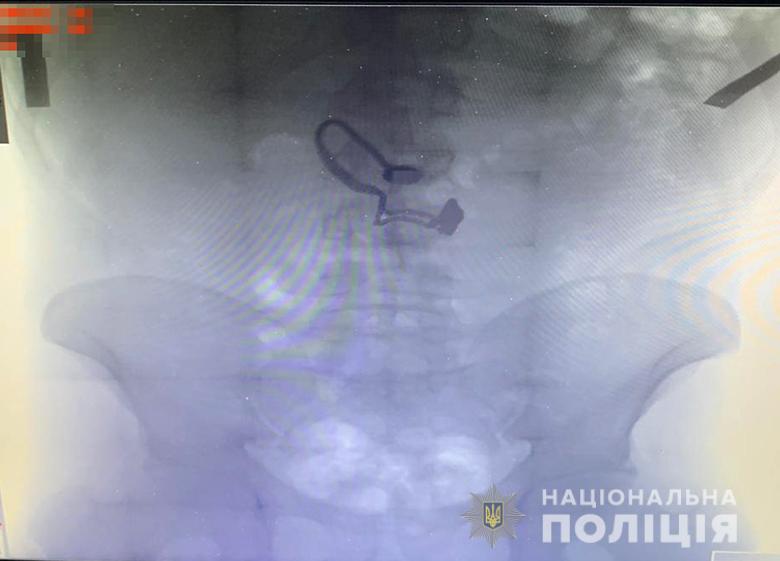

Грабителем оказался 26-летний житель Луганской области, ранее уже судимый за кражи. Его задержали. Во время поверхностного осмотра у мужчины нашли кошелек потерпевшей. Позже он признался полицейским, что сорванную цепочку проглотил.

"Во время медосмотра на рентген-снимке задержанного врачи обнаружили украшение", - сообщают в полиции.